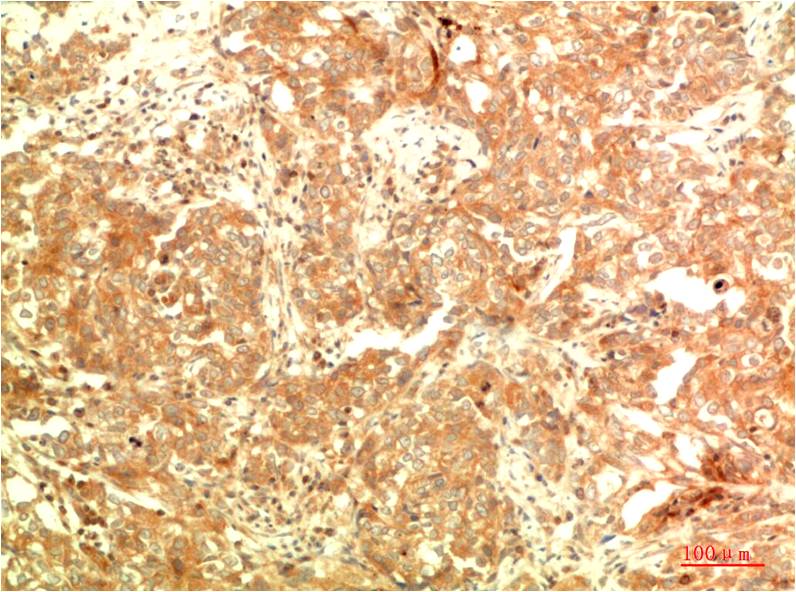

- Immunohistochemistry analysis of paraffin-embedded Human Ovarian Carcinoma Tissue using APG5L antibody.High-pressure and temperature Sodium Citrate pH 6.0 was used for antigen retrieval.